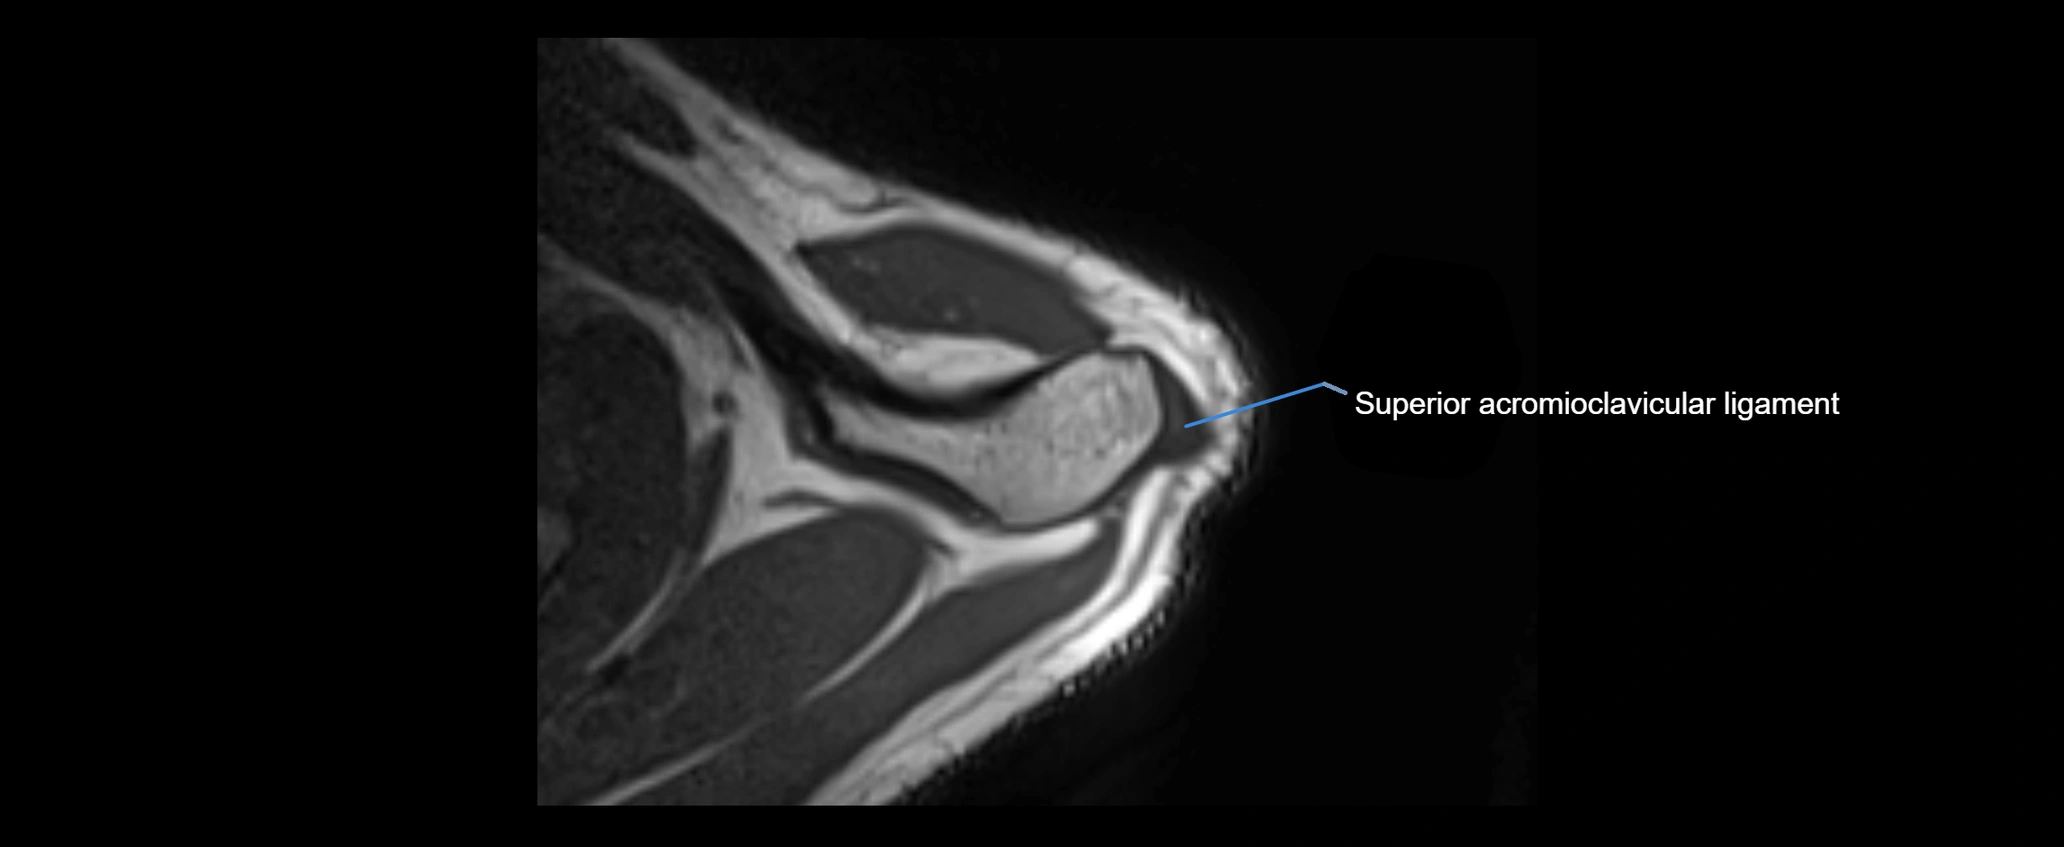

MRI images

image

MRI Appearance

• T1-weighted images:

• Normal ligament: Low signal (dark linear band) spanning acromion to clavicle.

• Surrounding fat planes: Bright, delineating the ligament clearly.

• Marrow of clavicle and acromion: Bright due to fatty content.

• Tears: Discontinuity or irregular thickening with intermediate-to-bright signal.

• Chronic injury: Thinning, fraying, or irregular low-signal fibers with adjacent scarring.